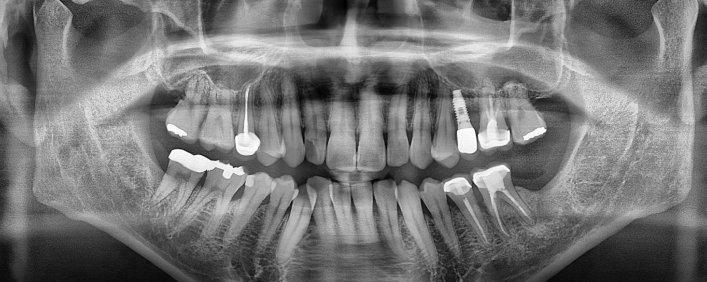

임플란트 치료사례

서울스마트치과는 결과로 증명합니다.

위 치료 사례는 서울스마트치과에서 직접 치료를 받고, 환자 본인의 동의를 얻어 게재된 사진으로 무단 인용, 도용, 재배포 시 민/형사상 책임을 질 수 있습니다.